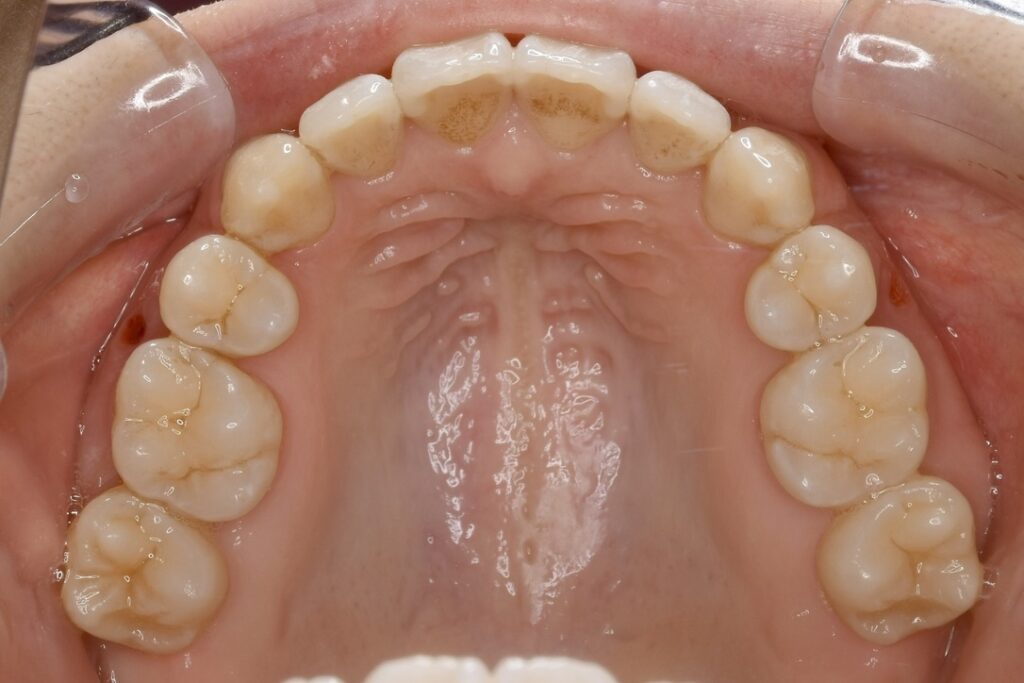

| 主訴 | 上の歯が前に出ている気がして気になる。 |

|---|---|

| 診断名・主な症状 | 叢生 |

| 年齢 | 23歳 |

| 治療内容 | 上の奥歯を後ろに引くことでできたスペースを利用して前歯のデコボコを解消しました。 |

| 使用装置 | 舌側矯正(ワイヤー) 表側矯正(ワイヤー) 矯正用ミニインプラント |

| 抜歯部位 | 抜歯なし |

| 治療期間 | 1年9ヶ月 |

| 通院回数 | 24回 |

| 費用 | 120万円程度(税別) 231 |

| リスク・副作用 | 痛み、歯肉退縮、歯根吸収、抜歯に伴う出血や腫れが生じることがあります。 |